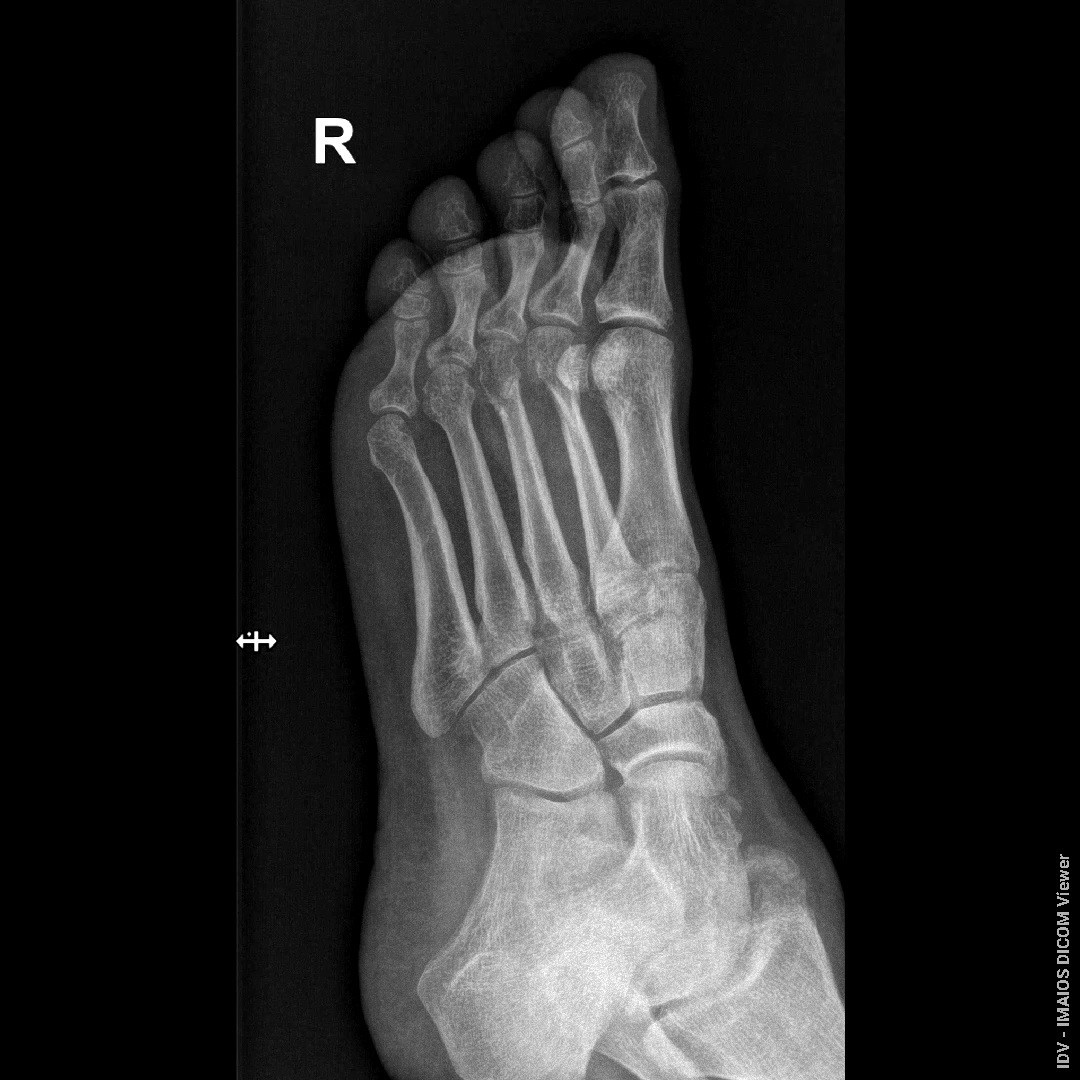

Здравствуйте, Доктор! Перелом был 23.06.2025. посмотрите пожалуйста снимки от 08.08.2025, срослись ли переломы, образовалась ли костная мазоль, можно ли начинать ходить?

Здравствуйте. По представленным снимкам видны признаки формирования костной мозоли в области перелома, что говорит о начале сращения однако линия перелома ещё прослеживается, и полное костное сращение скорее всего не завершено. Начинать ходить без опоры пока рано и нагрузку нужно увеличивать постепенно и только по разрешению лечащего травматолога после клинического осмотра и контрольного рентгена.